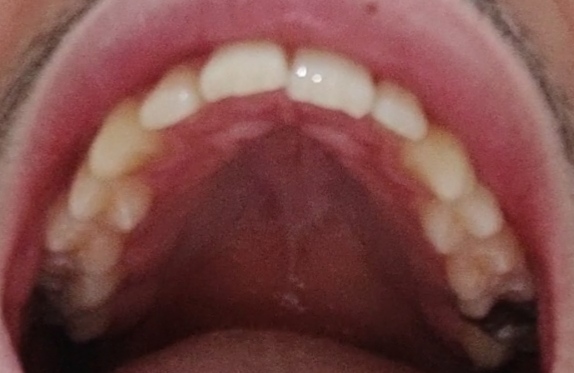

My golden ratio is 1.4 (I have narrow lips), when I smile only 6 teeth are visible and my teeth are not big, they are normaldo you have a good lip to nose ratio?

how many teeth show when your smiling and is it overall a nice smile?

are your teeth big? (usually if people have big teeth then they have less teeth showing)

yeah then chances are you have a narrow palate (it's fixable)My golden ratio is 1.4 (I have narrow lips), when I smile only 6 teeth are visible and my teeth are not big, they are normal

Damn, 12?? Brutal man. Anyways, are narrow lips also caused by a narrow palate?If you have a 6 tooth smile than yes. Ideal is 12 tooth smile. Get expandin'.